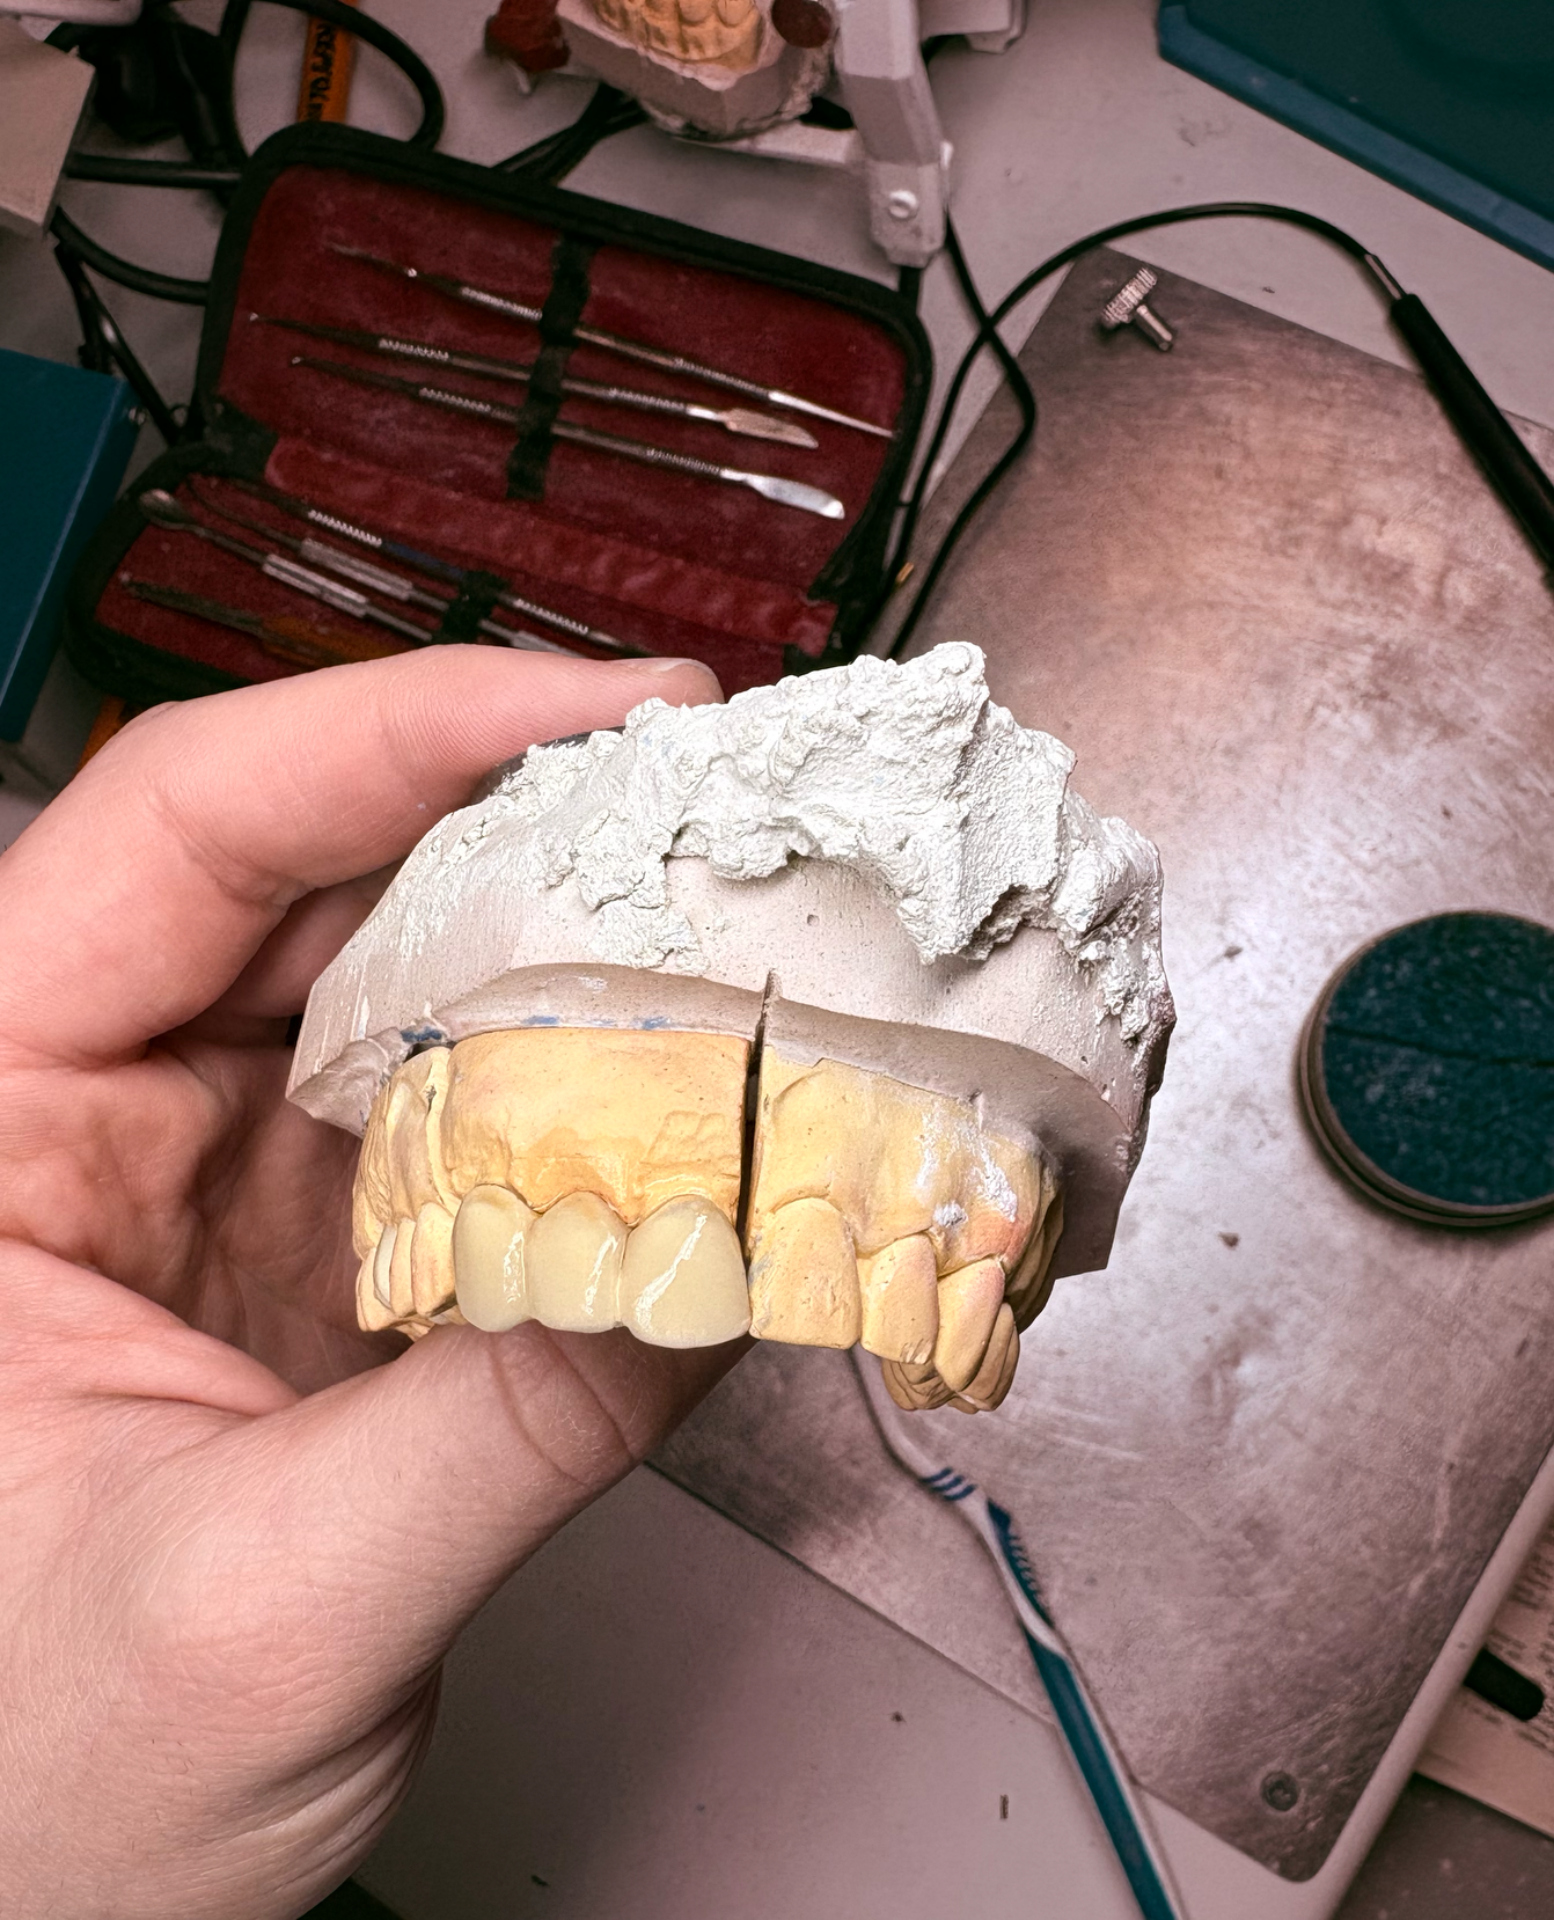

Molar provisional.

Modelado superior.